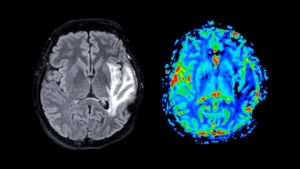

Parkinson’s disease, a chronic and progressive neurological affliction, impacts the lives of over a million individuals across...